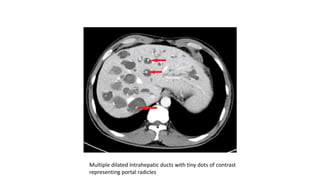

Central dot sign

-enhancing fibrovascular bundle of

portal vein radicles completely

surrounded by dilated bile ducts

Multiple dilated intrahepatic ducts with tiny dots of contrast

representing portal radicles

Central dot sign -enhancingfibrovascular bundle of portal vein radicles completely surrounded by dilated bile ducts

• 43.

Multiple dilated intrahepaticducts with tiny dots of contrast representing portal radicles